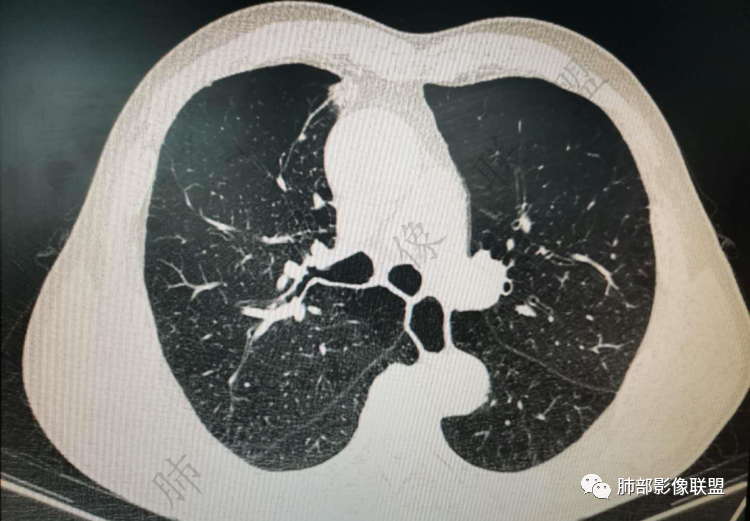

右肺上类圆形叶结节,周边见细软毛刺,增强后呈环形明显强化,内部坏死,邻近胸膜光滑,结合病史2个月明显增大,考虑炎性可能性大。

老年男性,炎性指标略高,肺气肿背景。右肺上叶胸膜下结节,部分边缘平直,部分稍模糊,软长毛刺,血管增粗,病灶中心密度减低,邻近脂肪间隙清晰。考虑炎性肉芽肿或慢性炎症,鉴别鳞癌。

老年男性,炎性指标略高,肺气肿背景。右肺上叶胸膜下结节,部分边缘平直,部分稍膨隆,供血血管增粗,增强扫描病灶中心密度减低,呈环形强化,邻近脂肪间隙清晰。考虑炎性肉芽肿或慢性炎症,鉴别鳞癌。

肺气肿背景

实性有隆起的小结节,内部有坏死、周围包括内乳动脉有增粗

右肺上叶前段胸膜下结节,边缘分叶毛刺,血管集束,支气管截断,纵膈胸膜牵拉,内乳动脉增粗,密度不均,中央可见坏死,两个月短期随访结节有增大,考虑恶性,腺癌。鉴别结核。

肺气肿背景,右肺上叶纵隔旁胸膜下结节,有血管集束,支气管堵塞,内乳动脉增粗,增强不均匀强化,内可见低密度区。考虑为恶性可能性大

老年男性,肺气肿背景,右肺上叶胸膜下弧立实性不规则结节,密度不均,其内低密度坏死影,支气管似有截断,血管集束,2月复查明显增大,考虑恶性,鳞癌可能大,鉴别炎性肉芽肿

老年男性,炎性指标略高。影像表现右肺上叶胸膜下结节,膨胀性生长部分边缘平直,边界清晰,病灶可见血管集束征,近段支气管阻断?增强扫描病灶中心密度减低,低密度区边界模糊,外围环形强化。老年性,不能排除恶性病变,周围性鳞癌,其次才考虑炎性肉芽肿或慢性炎症

老年男性患者。肺气肿 ,轻微的支气管扩张,右肺上叶前段胸膜下小结节影,轻分叶,长短不一毛刺,边界欠光整,明显的强化。考虑腺癌或鳞癌。

右上叶前段结节,肺气肿背景,血管滋养丶支气管截断,与纵隔脂肪间隙清析

老年男性,肺气肿背景,右肺上叶前段胸膜下结节,部分边缘毛糙,血管集束增粗,支气管似有截断,胸膜牵拉,结节密度不均,两个月随访结节有增大,考虑恶性,肺癌可能;另右肺上叶后段肋胸膜区小片状类结节影,考虑炎性可能。

老年男性,有肺气肿,估计有吸烟。病灶靠近胸膜宽基底紧贴胸膜。有直边征,有U型凹陷,为良性征象,有血管集数征,小的支气管截断征,为恶性征象。病灶周围没有树芽征,似乎找不到卫星灶,没有葫芦兄弟,增强扫描病灶内有空泡,所以综合考虑恶性可能大,鳞癌和粘液腺癌鉴别。良性的话结核和隐球菌鉴别。

右肺上叶前段结节,边缘毛糙,血管进入,局部细支气管似闭塞,增强有强化,中心密度似减低,2月明显增大,肺气肿背景,首先考虑炎性结节,鳞癌增大可以很快,对比老片看看

右肺上叶前段胸膜下结节,近段支气管截断,血管伸入结节内,密度不均,同侧临近内乳动脉增粗,不均匀强化,肺气肿背景,两月明显增大,考虑低分化鳞癌,隐球菌代排

老年男性,肺气肿背景,右肺前上纵隔旁结节,边缘平直,密度均匀,伴长索条影,增强均匀轻中度强化,结合2个月结节明显增大,倍增时间短,腺癌不考虑,考虑炎性肉芽肿,鉴别炎性肌纤维母细胞瘤

老年男性,白细胞计数及CRP稍高,右肺上叶结节,两个月来有增大,部分边缘可见边界模糊的GGO,局部边缘平直、凹陷,临近胸膜增厚,内见坏死,坏死区边界未见明显壁结节,壁较厚而且均匀强化,支气管似乎有扩张然后截断,近端血管增粗明显。考虑炎性病变,脓肿?有结核病人密切接触史,注意是否为结核。有点难以理解的是为什么右侧内乳动脉增粗明显。

老年男性,无症状,炎性指标增高。肺气肿背景,右肺上叶前段结节,边缘部分平直部分澎隆,血管集束,支气管至病变边缘似截断,近端扩张。增强环形强化,中心坏死。两月内病灶增长太快,考虑炎性肉芽肿,慢性脓肿?结核?癌待排。

支气管变形、壁增厚,提示慢性支气管炎症

边缘平直

宽基底与胸膜相连,附近胸膜增厚,糊墙

内乳动脉关系似乎不密切

内部有低强化区,边界尚清

还是支持炎性放前面,恶性待排